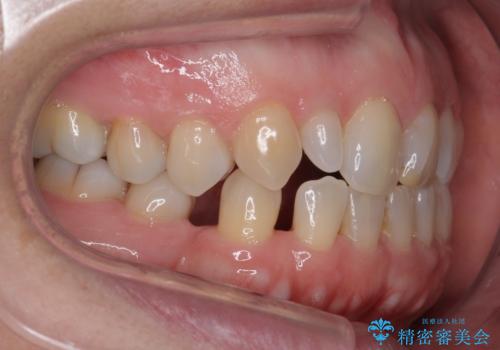

矮小(わいしょう)歯の形をセラミックで自然に 50代女性

- 右上の2番目の前歯がとがった形をしていたため、セラミックで形を整えています。

短くてとがった歯の形が反対側と同じ形となり、左右対称となり、ずいぶん自然な印象になりました。

下の前歯とのかみ合わせが切端咬合だったため、前歯の部分矯正も併せて行っています。(費用別途)